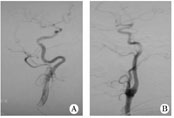

1.1对象2011-08至2012-02在我院住院的缺血性脑卒中患者,经脑血管造影筛选出年满18周岁、颈内动脉迂曲(颈内动脉弯曲如螺旋状或有2个或2个以上的弯曲)、而无狭窄或闭塞的患者30例(迂曲组,图1A),无颈内动脉迂曲、狭窄或闭塞的患者30例(无迂曲组,图1B)。所有患者在脑血管造影前均签署手术知情同意书。

图1患者颈内动脉血管造影

A迂曲;B无迂曲